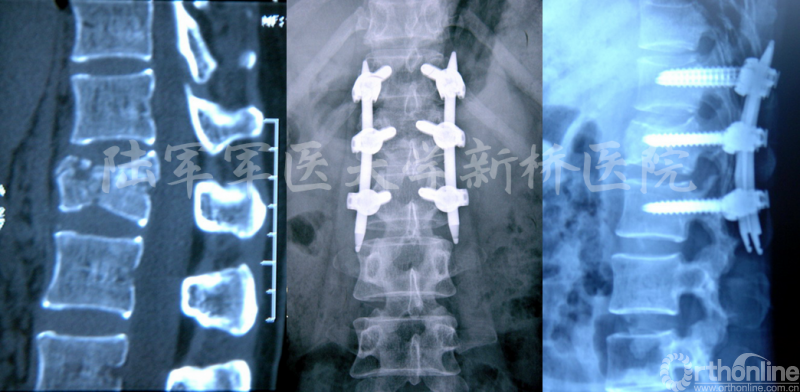

因胸腰椎骨折常伴脊柱后凸畸形,但原有Sextant系统仅具备撑开加压功能,而不具备提拉复位作用,新型的经皮螺钉技术Sextant-R克服了此缺陷,具有畸形矫正和提拉复位作用,已取得满意临床效果[9]。

Zhang W, LI HY, Zhou Y, et al. Spine 2016,41(19B):23-29.